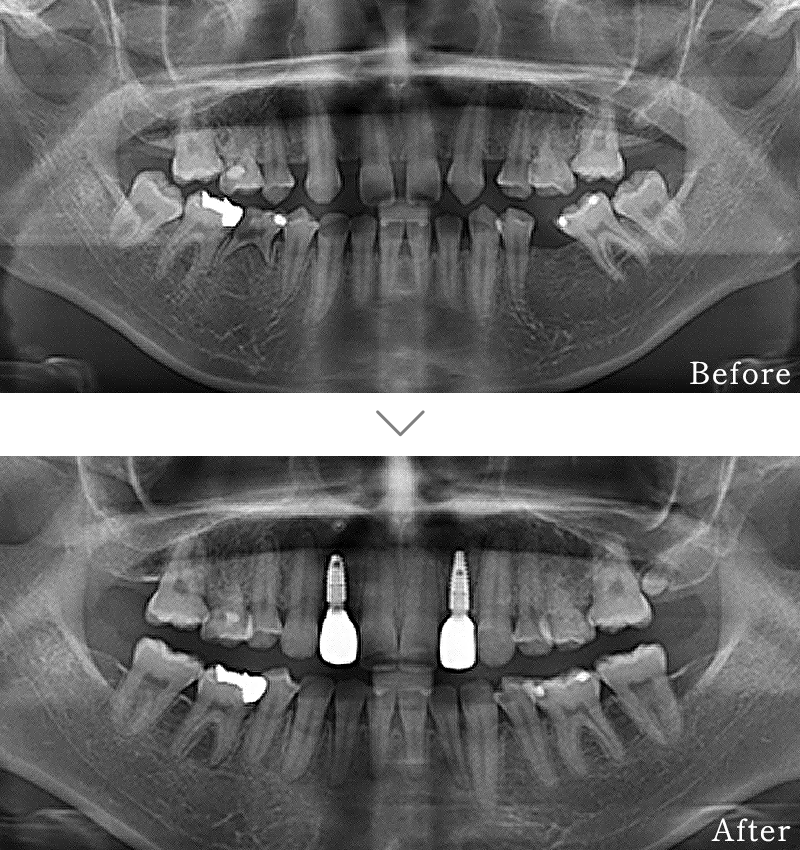

CASE3

主訴 歯の本数が少なく、全体的に隙間があいている。

治療法 矯正治療後に上にインプラント2本使い、噛み合わせと見た目を回復しています。インプラント部位は骨が薄かったため、造骨処置(GBR)と歯肉移植(CTG)を行なっています

治療期間 10ヶ月

※矯正治療の期間は含まれておりません。

費用 CT:16,500円(税込)

+ インプラント治療:1,051,600円(税込)

+ 造骨処置(GBR):176,000円(税込)

合計:1,244,100円(税込)

※矯正治療費は含まれておりません。

副作用

• 歯周病に感染・発症し重度に進行するとインプラントが抜けてしまうことがあります。

• 手術後は数日間腫れが出る場合があります。

• 歯肉移植時は、採取部位からの出血が数日続くことがあります。